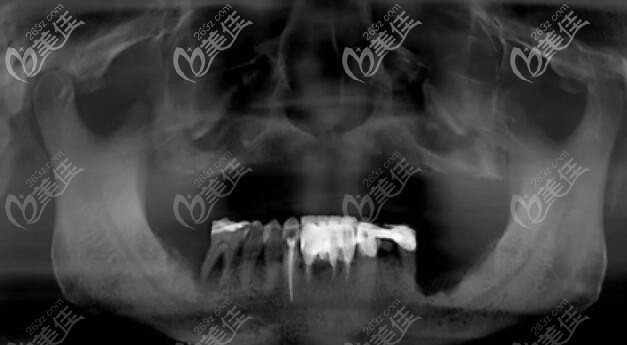

上半口做种植牙后的CT照片↓↓↓